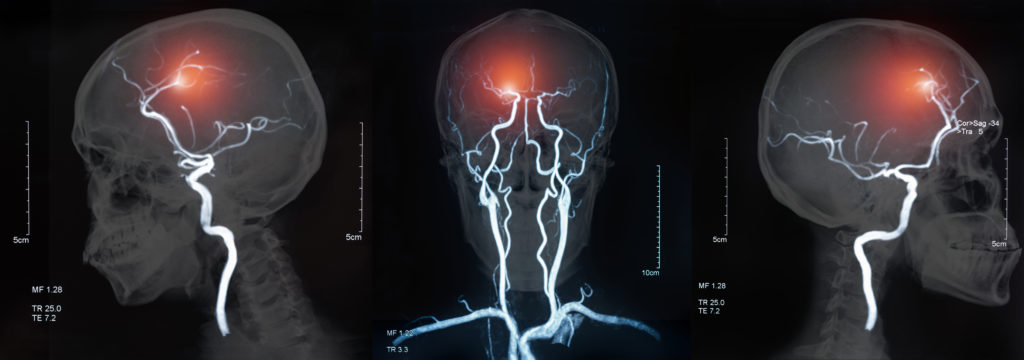

Der Schlaganfall ist eine der häufigsten Todesursachen der westlichen Welt. In Niederösterreich erleiden rund 4600 Patienten pro Jahr ein solches Ereignis. Die Aussage ” Time is brain” verdeutlicht einmalmehr die versorgungskritische Relevanz in der Präklinik. Die E-Learning Einheit wurde im Auftrag des Niederösterreichischen Gesundheitsfonds (NÖGUS) von der FH St. Pölten Department für Gesundheit erstellt und uns zur Verfügung gestellt.